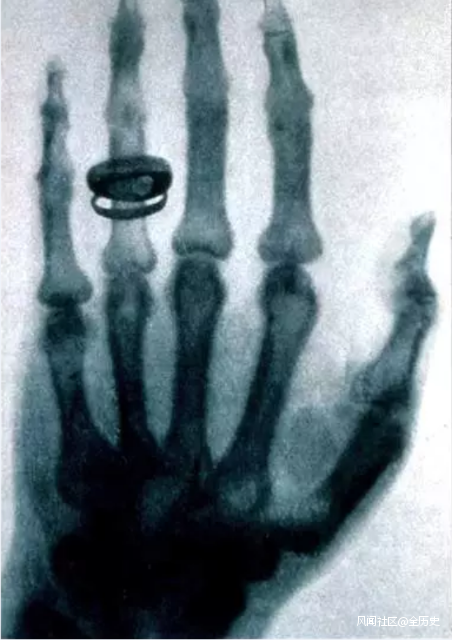

倫琴在X光下的手部照片

還有説特斯拉早於倫琴發現了X射線的。特斯拉確實研究過X射線不假,但他大部分跟X射線有關的研究資料都毀於了實驗室的一場大火。

關於他研究X射線到什麼程度,已經沒法證實了。